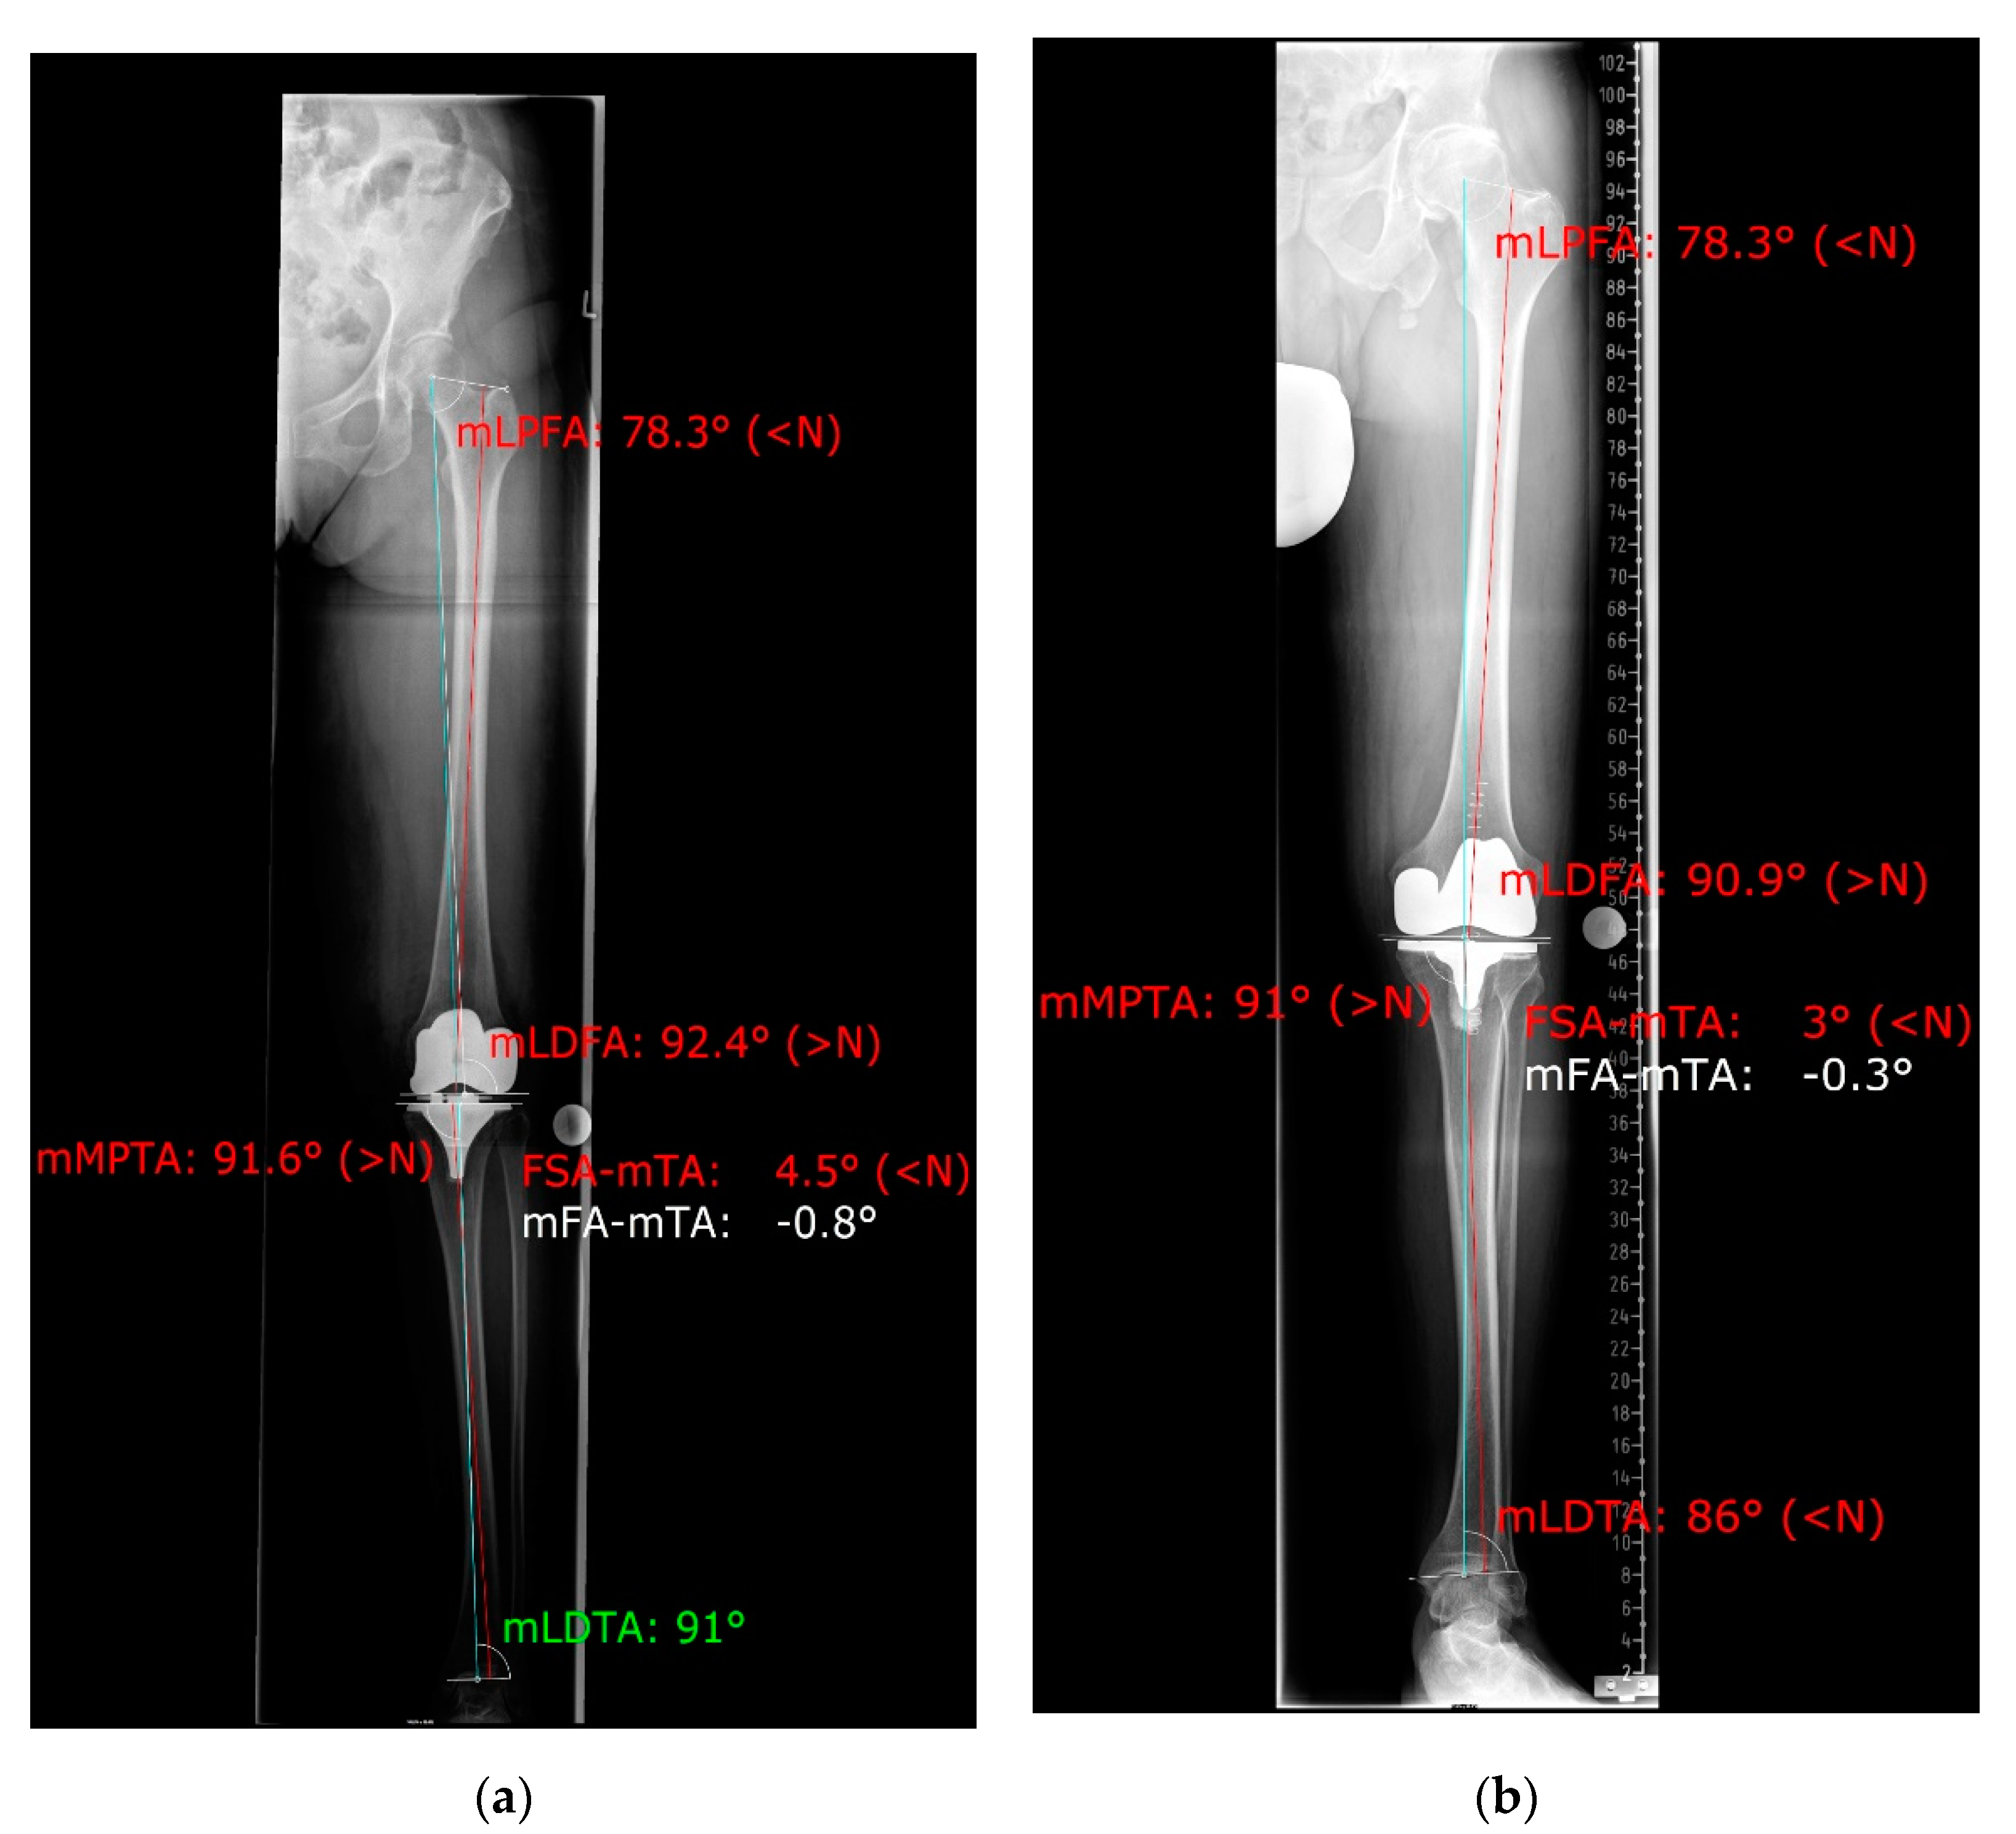

3.1. Rotational Correction

3.2. Coronal Alignment